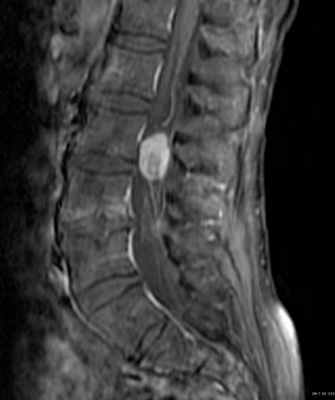

Эпендимомы экстрамедуллярной локализации растут из конуса и конечной нити. По гистологии относятся к миксопапиллярному типу. Составляют около 13% от всех спинальных эпендимом. Диагностируются в возрасте около 40 лет и чуть чаще у мужчин. Хотя относятся к градации 1, встречается диссеминация с током ликвора.

На Т1-взвешенных МРТ поясничного отдела позвоночника эпендимомы изоинтенсивны спинному мозгу. На Т2-взвешенных МРТ они гиперинтенсивны. Обычно хорошо и равномерно контрастируются, хотя встречается и периферический тип усиления. Изредка встречается субарахноидальная диссеминация. Может наблюдаться высокое содержание белка в ликворе, что проявляется повышенным сигналом от него на Т1-взвешенных МРТ. При этом корешков не видно. Описаны при эпендимоме субарахноидальные кровоизлияния с характерными депо гемосидерина по поверхности вовлеченных структур.

МРТ поясничного отдела позвоночника. Миксопапиллярная эпендимома. Т1-взвешенная МРТ после контрастирования. Увеличение.